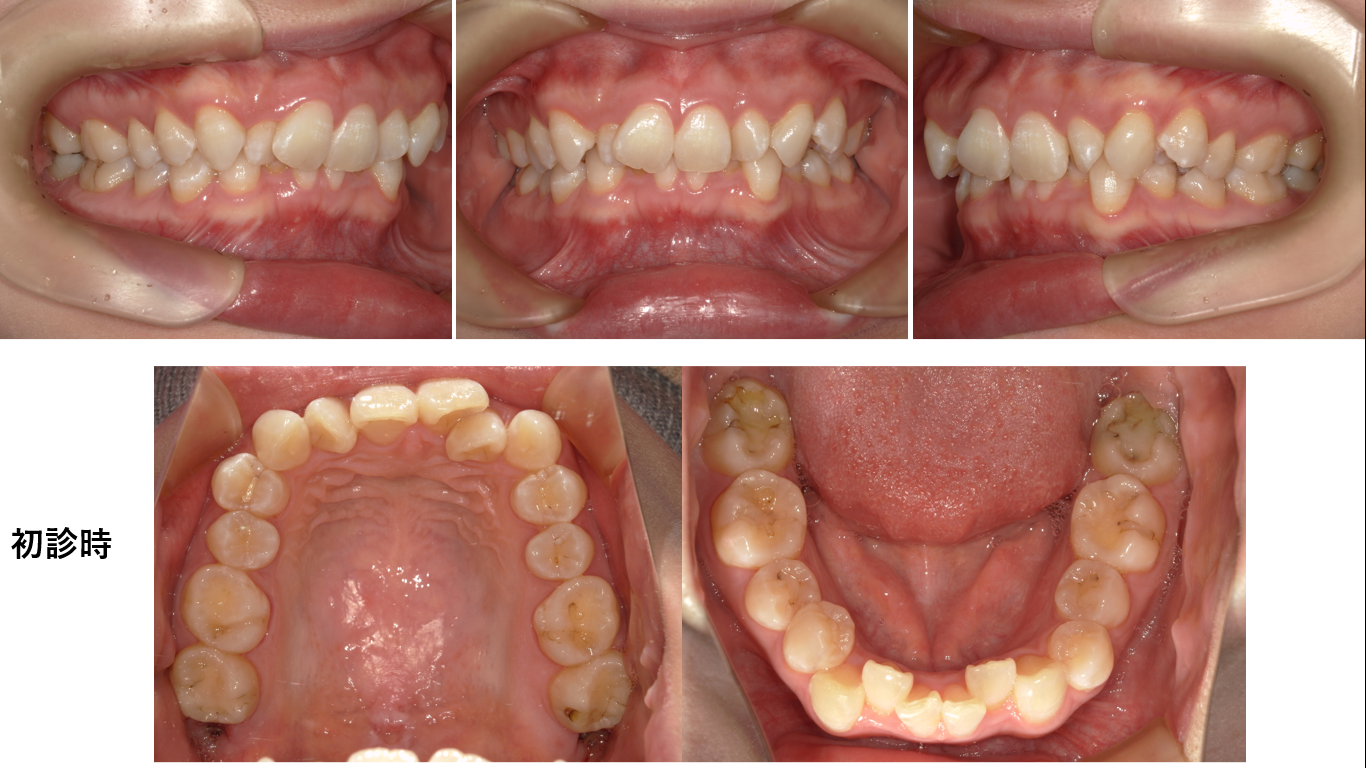

矯正症例144 AngleⅡ級2類

初診時32歳 抜歯部位上下左右4番、8番、治療期間2年8か月、治療費総額1,120,000(税込み)